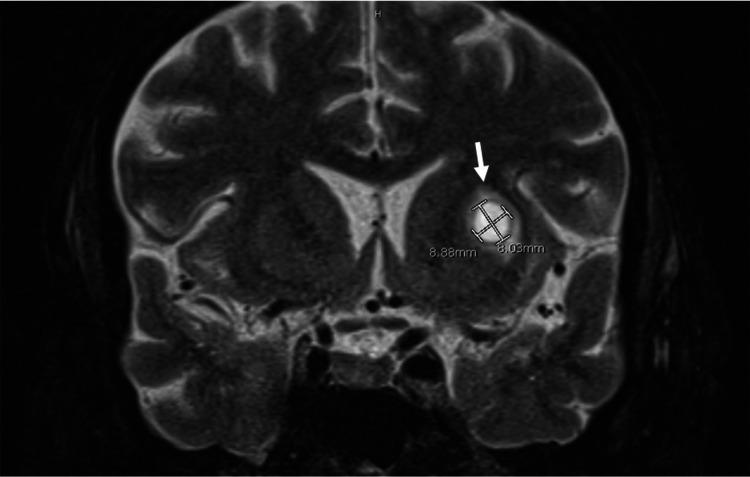

库欣综合征(CS)是一种免疫功能低下状态,其特征为因皮质醇增多症导致细胞免疫和适应性免疫受损。免疫系统的这种失衡会导致机会性感染的高风险,而这些感染可能会致命。对于此类患者,通过早期诊断和有效控制潜在的皮质醇增多症可降低死亡率。在本病例报告中,我们描述了如何通过低剂量持续输注依托咪酯迅速降低皮质醇水平,这对一名患有库欣综合征的29岁女性有效治疗机会性感染——播散性诺卡菌病起到了关键作用。我们还讨论了使用抗生素治疗,包括用亚胺培南和磺胺甲恶唑/甲氧苄啶(SMX/TMP)进行经验性治疗,以及根据药敏试验用阿米卡星、SMX/TMP和强力霉素进行确定性治疗,如何有助于预防不良后果。通过这个病例,我们旨在强调,库欣综合征患者胸部计算机断层扫描(CT)上的浸润或空洞性病变应引起对诺卡菌病的关注,并应立即开始用抗生素进行治疗。同样,播散性诺卡菌病应始终引起对可能的免疫缺陷状态如库欣综合征的关注。我们的病例独特之处在于详细阐述了在患有内源性库欣综合征和广泛侵袭性机会性感染的患者中使用依托咪酯急性降低皮质醇水平的重要性。在本病例中,依托咪酯的药理学方面已发表在《药学实践杂志》上,并在本文中适当引用。

https://cdn.ncbi.nlm.nih.gov/pmc/blobs/3a1b/8729312/6be9fc1620b3/cureus-0013-00000020214-i03.jpg

https://cdn.ncbi.nlm.nih.gov/pmc/blobs/3a1b/8729312/9a38a14fcc1c/cureus-0013-00000020214-i01.jpg

https://cdn.ncbi.nlm.nih.gov/pmc/blobs/3a1b/8729312/ea99b29df897/cureus-0013-00000020214-i02.jpg